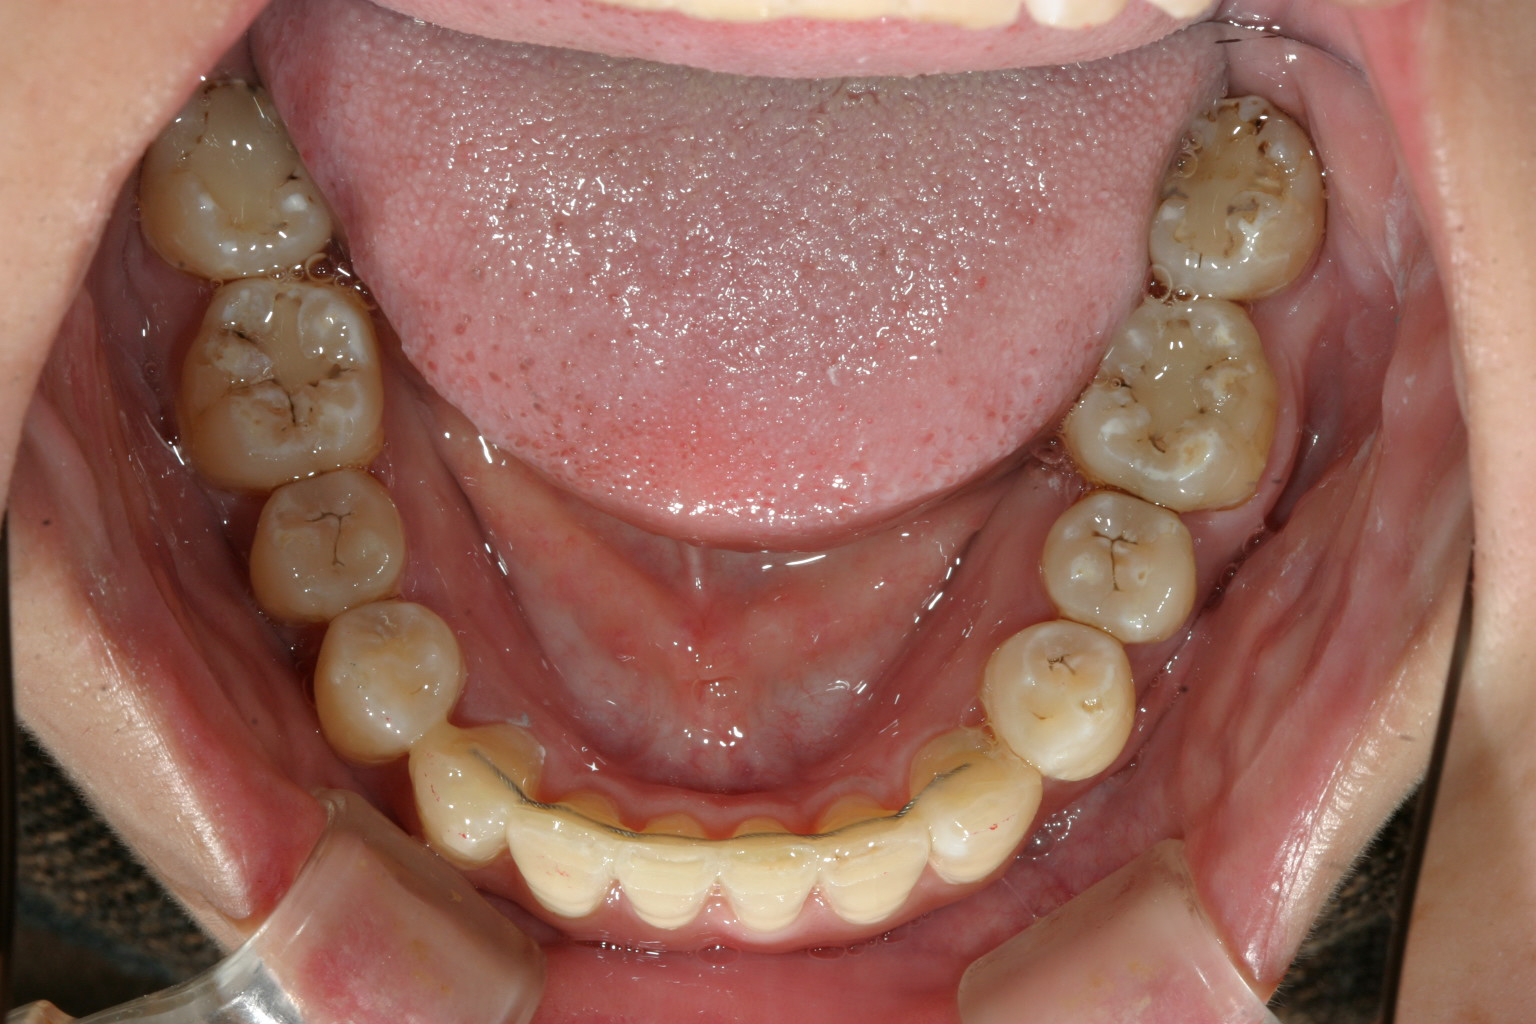

下顎は非抜歯で叢生改善してます。

綺麗な側面観です。